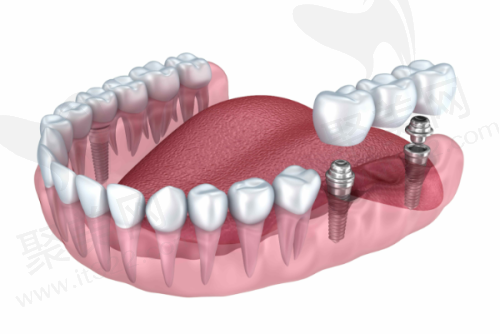

单颗种植

多颗种植